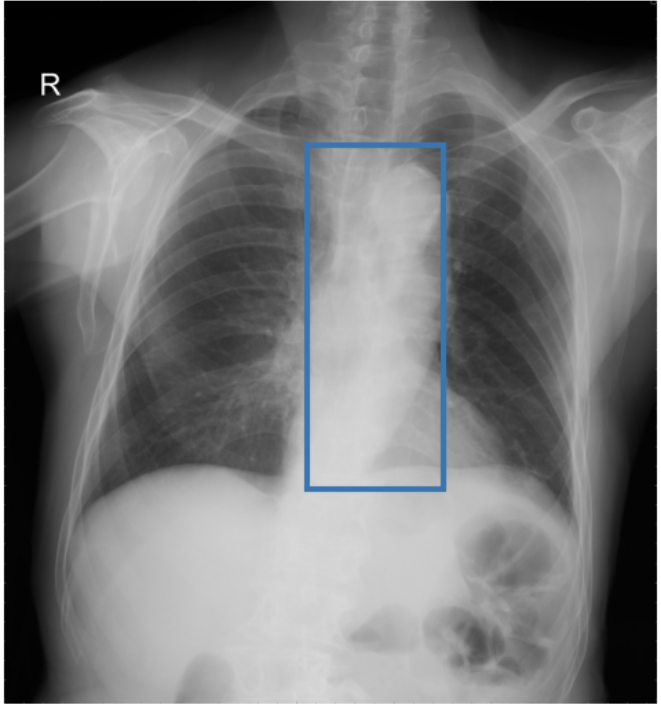

To address these drawbacks, state-of-the-art models such as MAIRA-2 [3] explicitly incorporate grounded report generation to better align local visual evidence with the textual findings. For example, MAIRA-2 is trained on a diverse set of localization-based tasks, including phrase grounding and grounded report generation. However, as shown in Figure 1, current models often exhibit a bias in which the target visual regions become overly associated with abnormal findings, leading to false positives in medical reports.

As shown in Table 1, our data composition reflects this imbalance: over 12.9M instances from Chest ImaGenome dominate the much smaller MS-CXR (815 PG instances) and PadChest-GR (12k instances) datasets. Beyond the imbalance between datasets, each dataset also exhibits substantial intra-dataset class imbalance. For example, anatomical regions in AGRG and semantic categories in PG are unevenly represented, leading the model to overfit frequent regions, neglect rare but clinically important ones, and hallucinate findings (Figure 1). Our curriculum framework addresses both sources of imbalance.

While MAIRA-2 exhibits a slightly lower hallucination rate for a few anatomies (e.g., ‘Cardiac Silhouette’), CURE consistently achieves a significantly lower contradiction rate and higher entailment rate across almost all categories. This improved performance likely stems from a key difference in the training data composition. Standard phrase grounding, used by MAIRA-2, is inherently biased towards abnormal findings. In contrast, our AGRG formulation exposes the model to both normal and abnormal descriptions for each anatomical region, leading to a more balanced and reliable generative process that mitigates the tendency to hallucinate abnormalities.

Figure 3 shows phrase grounding results for the phrase “Chronic inflammatory changes predominantly in both lung apices” on an image from PadChest-GR [11]. Both CURE and MAIRA-2 successfully identify the lung apices associated with the described findings. However, CURE’s localization is more accurate and better aligned with the phrase semantics, while MAIRA-2 provides a coarser prediction that only partially covers the relevant areas. As expected, MedGemma-4B-IT does not produce visual grounding outputs, and thus no bounding boxes are shown for this model.